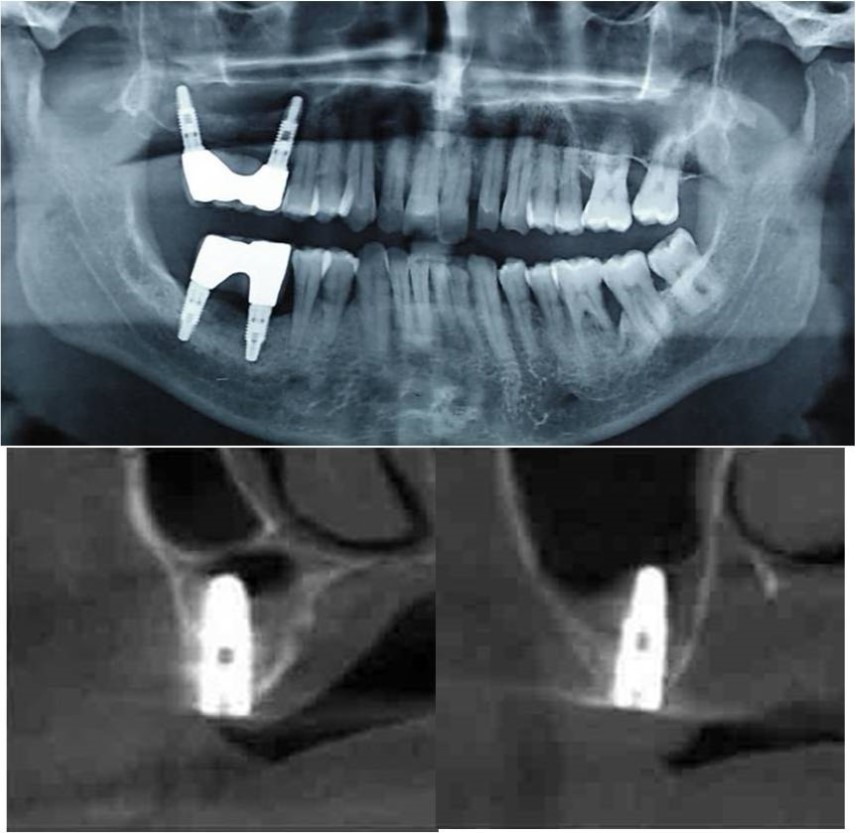

Treatment: Direct sinus augmentation using calcium phosphosilicate (CPS) in relation to 16,17 followed by implant placement as a single step procedure was advised. Lateral window was created and calcium phosphosilicate putty (2cc) was dispensed as the graft material through the lateral osteotomy site to maintain the elevated sinus membrane followed by placement of two dental implants through the crestal approach measuring 3.75 x 11.5mm under local anaesthesia and strict aseptic protocols. At the end of 6 months, a repeat CBCT scan was advised to evaluate the increase in bone height. (Figure 7a-c, pre-treatment; Figure 8a-c, post-treatment)

Figure 8.(a-c) Post-treatment OPG and cross sections of CBCT showing residual alveolar bone height for Case No.1;

Case Report 2:

A 42 years old male patient reported to the Department of Oral and Maxillofacial Surgery, D.A.P.M.R.V Dental College and Hospital with a chief complaint of inability to chew food because of missing teeth in upper right and left back tooth regions from past one year. The teeth were extracted an year ago because of gross loss of tooth structure and poor prognosis for root canal treatment. Patient was a hypertensive since 4 years and was on medication for the same. Patient did not give history of any existing sinus pathologies. All possible rehabilitative options were explained to the patient and a treatment plan of replacement of missing teeth with implant supported prosthesis using one dental implant in 17 region was finalized.

Clinical and Radiological Assessment:

1.Partially edentulous maxillary and mandibular arches with missing 17, 26, 45, 46;

2.Increased pneumatisation of right maxillary sinus;

3.Height of available bone- 6.6mm;

4.Transverse thickness of available bone (CBCT evaluation)- 11mm;

5.Inter-ridge space adequate to place implant (10mm).

Treatment:

Patient underwent the procedure of indirect sinus elevation using sinus osteotomes in relation to 17 region. Calcium phosphosilicate putty was dispensed as the graft material through the crestal osteotomy site to maintain the elevated sinus membrane followed by placement of a dental implant measuring 5 x 10mm under local anaesthesia and strict aseptic protocols .The implant was allowed to osseo-integrate for a period of six months during which the patient was followed-up periodically and was assessed for peri-implantitis, crestal bone loss and mobility. At the end of 6 months, a repeat CBCT scan was advised to evaluate the increase in bone height. (Figure 9a,b, pre-treatment; Figure 10a,b, post-treatment)

Figure 9.(a,b) Pre-treatment OPG and cross section of CBCT showing residual alveolar bone height for Case No.2

Figure 10.(a,b) Post-treatment OPG and cross section of CBCT showing residual alveolar bone height for Case No.2